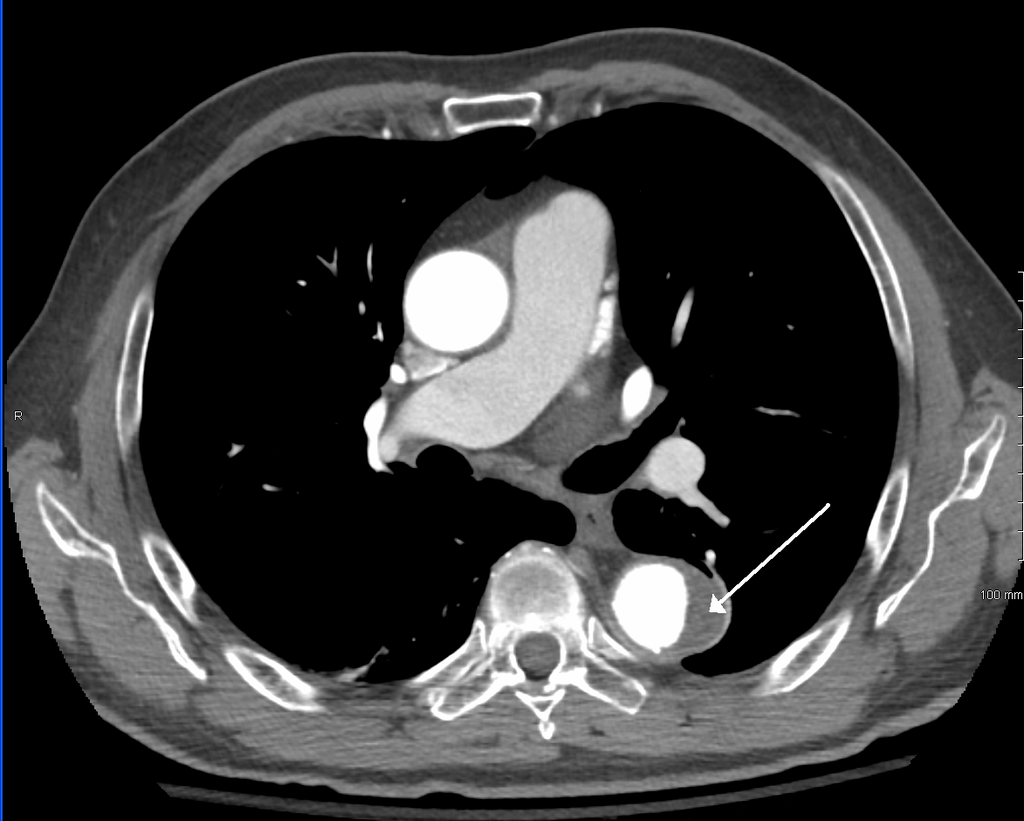

The image below presents what a CT scan looks like for a patient with a type B dissection (author James Heilman, MD): the area outlined by the arrow is the dissection’s false lumen. This new route shrinks up the aorta and decreases the blood supply in the aorta (the white part next to the false lumen, which is quite smaller in comparison to how wide the aortic root is at the center of the image):

CT scan presenting a dissected aorta. The bright round shape is the true lumen, where blood naturally flows. The area pointed by the arrow is the false lumen, where blood can accumulate and create clots, or flow and build up pressure later on the intima wall to create a secondary tear, enabling the blood to re-enter the true lumen.